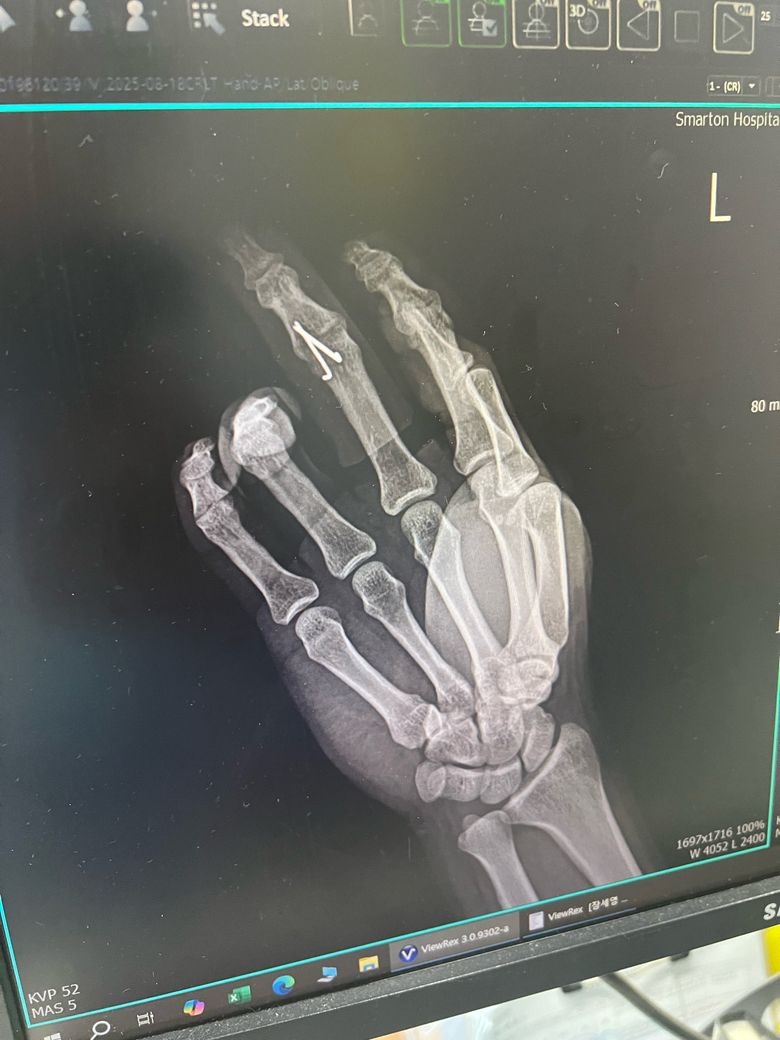

수술 전과 후 엑스레이 사진인데 잘 된건가요?

엑스레이상 핀만 박았지 골절나서 빠진 뼈부분은 그대로인거같아서요. 확인 좀 부탁드립니다. 그리고 혹시나 추후에 핀을 뽑을때는 어땋게 뽑나요

엑스레이상 핀은 골절 부위 고정으 위해 잘 박힌 것으로 보이지만 뼈 조각이 조금 남아 있는 경우도 있어 뼈가 자연적으로 붙을 때까지 관찰이 필요합니다.

수술 직후에는 일부 틈이 보여도 회복 과정에서 채워질 수 있어요 핀 제거는 작은 절개나 구멍을 통해 핀을 잡아 빼는 방식으로 간단하게 진행됩니다. 담당 의사가 뼈 유합 상태를 확인 후 안전하게 제거 시기를 결정합니다!